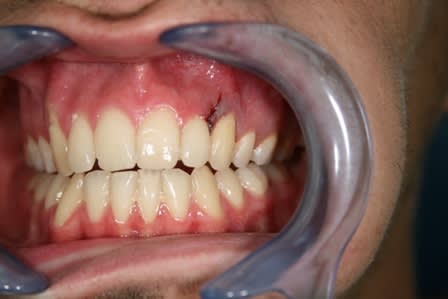

Quelque chose comme cela, qui doit rester souple. Fil fin en alliage nickel-titane et collage résine ou composite.

Patient de 20 ans venu en Urg cette après midi:

dent perdue temps moins de 2h

Suite à appel gardée en bouche

Bio réalisée dans une compresse stérile

Réimplantation après rinçage alvéole sérum Phy

Contention au Ribbond + compo , pas facile quand çà saigne

AB pendant 6 jours + Chx.

J'ai juste un doute en ce qui concerne l'hypochlorite , je ne m'en suis pas servi pour rincer le canal de peur de finir d'achever les quelques fibroblastes présents sur le cément du coup j'ai rincer le canal au sérum phy.

désolé pour l'ordre des photos